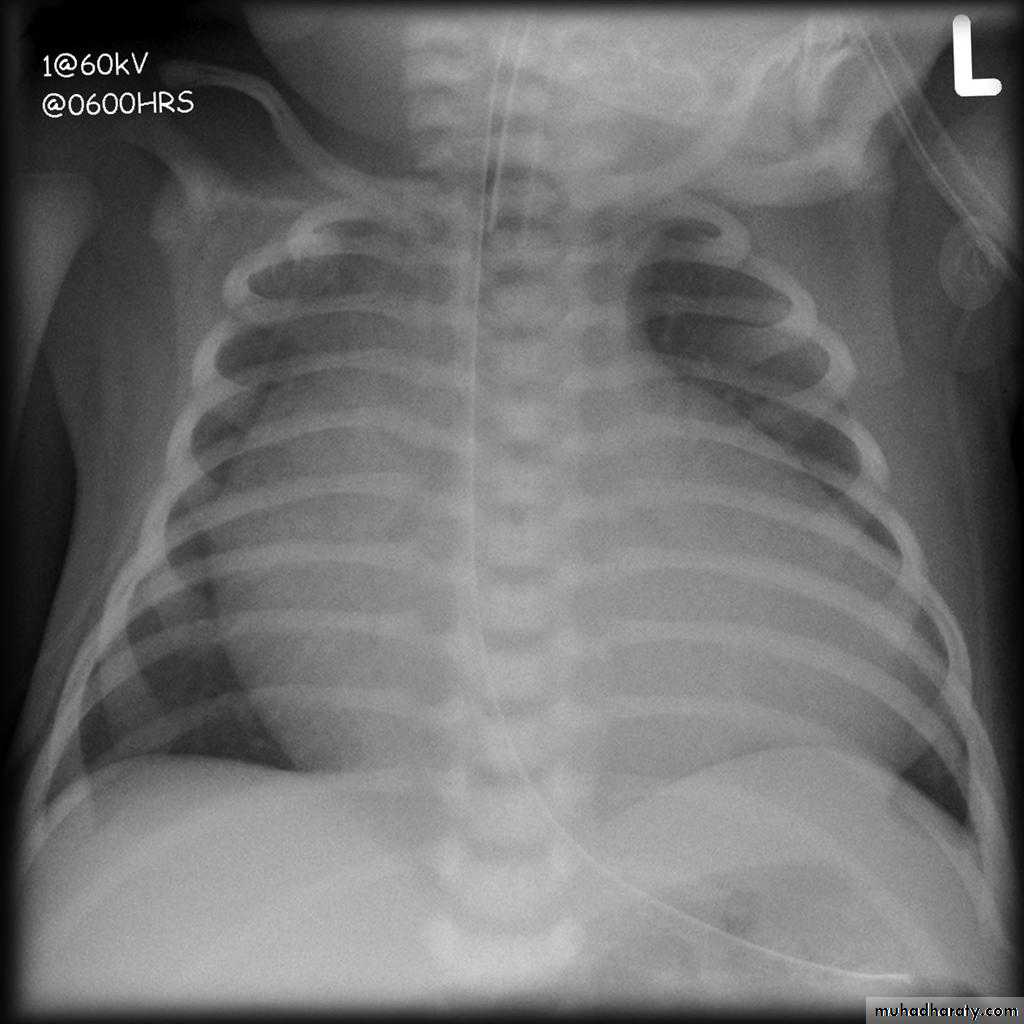

Normal thymus gland ( sail shape sign )